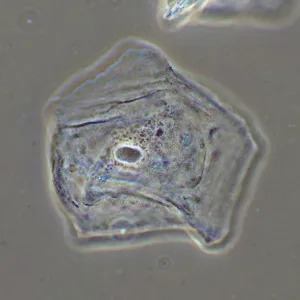

Фазово-контрастное устройство MAGUS SPH2 – это набор аксессуаров, которые позволяют реализовать на микроскопе MAGUS метод фазово-контрастной микроскопии. Фазовый контраст применяют для изучения прозрачных объектов, слабо различимых в светлом поле. Этот метод не требует окрашивания, повреждающего структуру живых образцов, поэтому подходит для широкого круга медицинских и фармакологических исследований.

Фазовый объектив имеет существенное конструктивное отличие от штатного объектива микроскопа – в нем присутствует фазовое кольцо, которое находится в плоскости выходного зрачка. В комплект ФКУ включены 4 объектива – с увеличением 10х, 20х, 40х и 100х. Все объективы рассчитаны на бесконечность и являются планахроматами, т. е. обеспечивают высокую степень выравнивания поля зрения (до 90%) и эффективно минимизируют сферические и хроматические искажения. Парфокальная высота объективов – 60 мм.

Объективы 10х, 20х и 40х являются «сухими», т. е. не требуют использования иммерсионного масла, а объектив 100х – масляный. Объективы 20х, 40х и 100х спроектированы для работы с покровным стеклом толщиной 0,17 мм, объектив 10х нетребователен к наличию покровного стекла – оно может быть, а может и не быть.